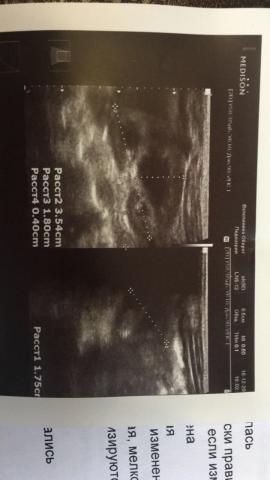

Если можно, то немного подробнее. На основании чего вам поставили такой диагноз, только на основании проведенного УЗИ? Может быть, собаке брали какие-то анализы? Если да, то выложите, пожалуйста, здесь их результаты. Если только данные УЗИ, то это разговор ни о чем (я имею ввиду панкреатит). Гастрит по данным УЗИ вообще не ставят.

К сожалению, ничего не могу рассмотреть. Попробуйте сами прочесть описание с фото. Если сможете, сделайте снимок более качественным. Или можно снять крупнее по частям. Может быть, тогда буквы будут видны более четко.

Спасибо, фотографии четкие. Я все прочитал. Как я и думал, там и "не пахнет" никаким гастродуоденитом, а тем более, панкреатитом.